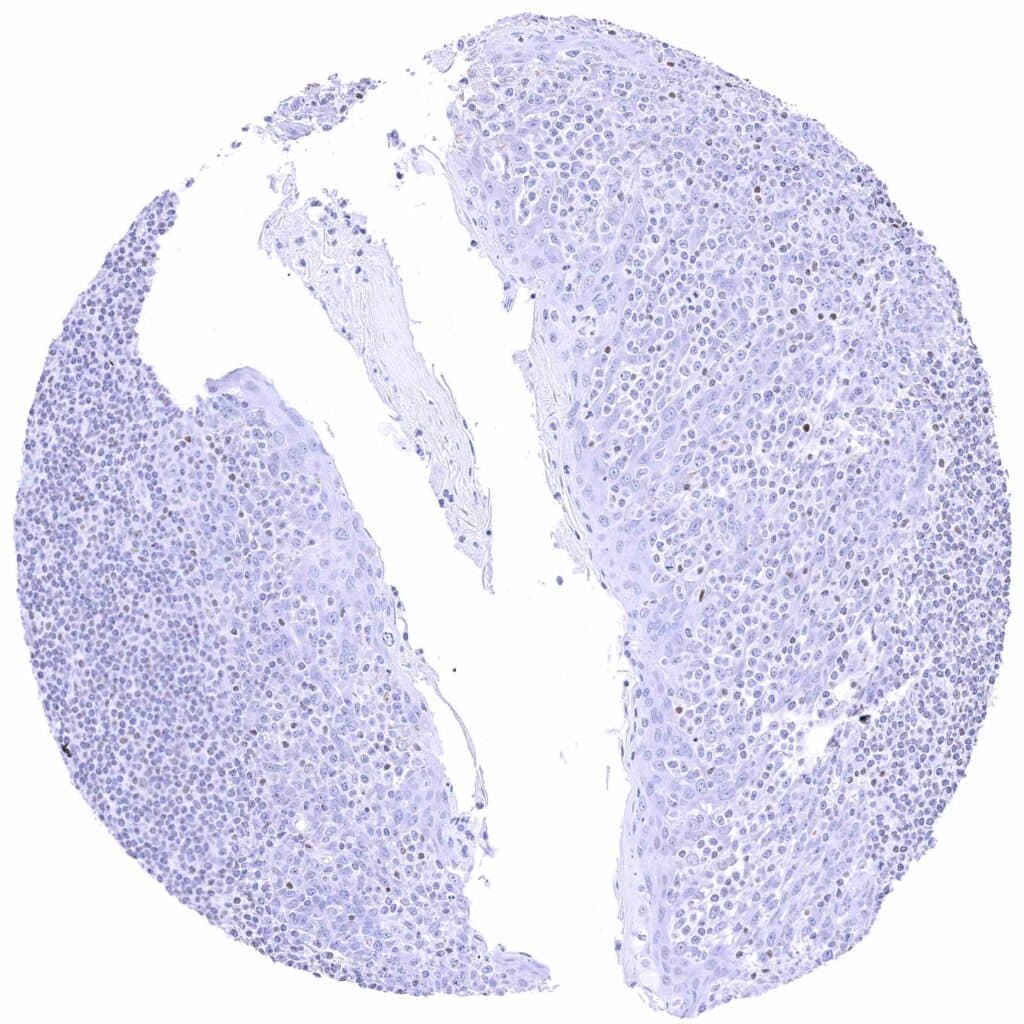

Uterus, ectocervix – Weak to moderate nuclear GATA3 staining of squamous epithelial cells.

Uterus, endocervix – Granular cytoplasmic GATA3 positivity of epithelial cells.

Uterus, endometrium (proliferation) – Granular cytoplasmic GATA3 positivity of some endometrial epithelial cells.